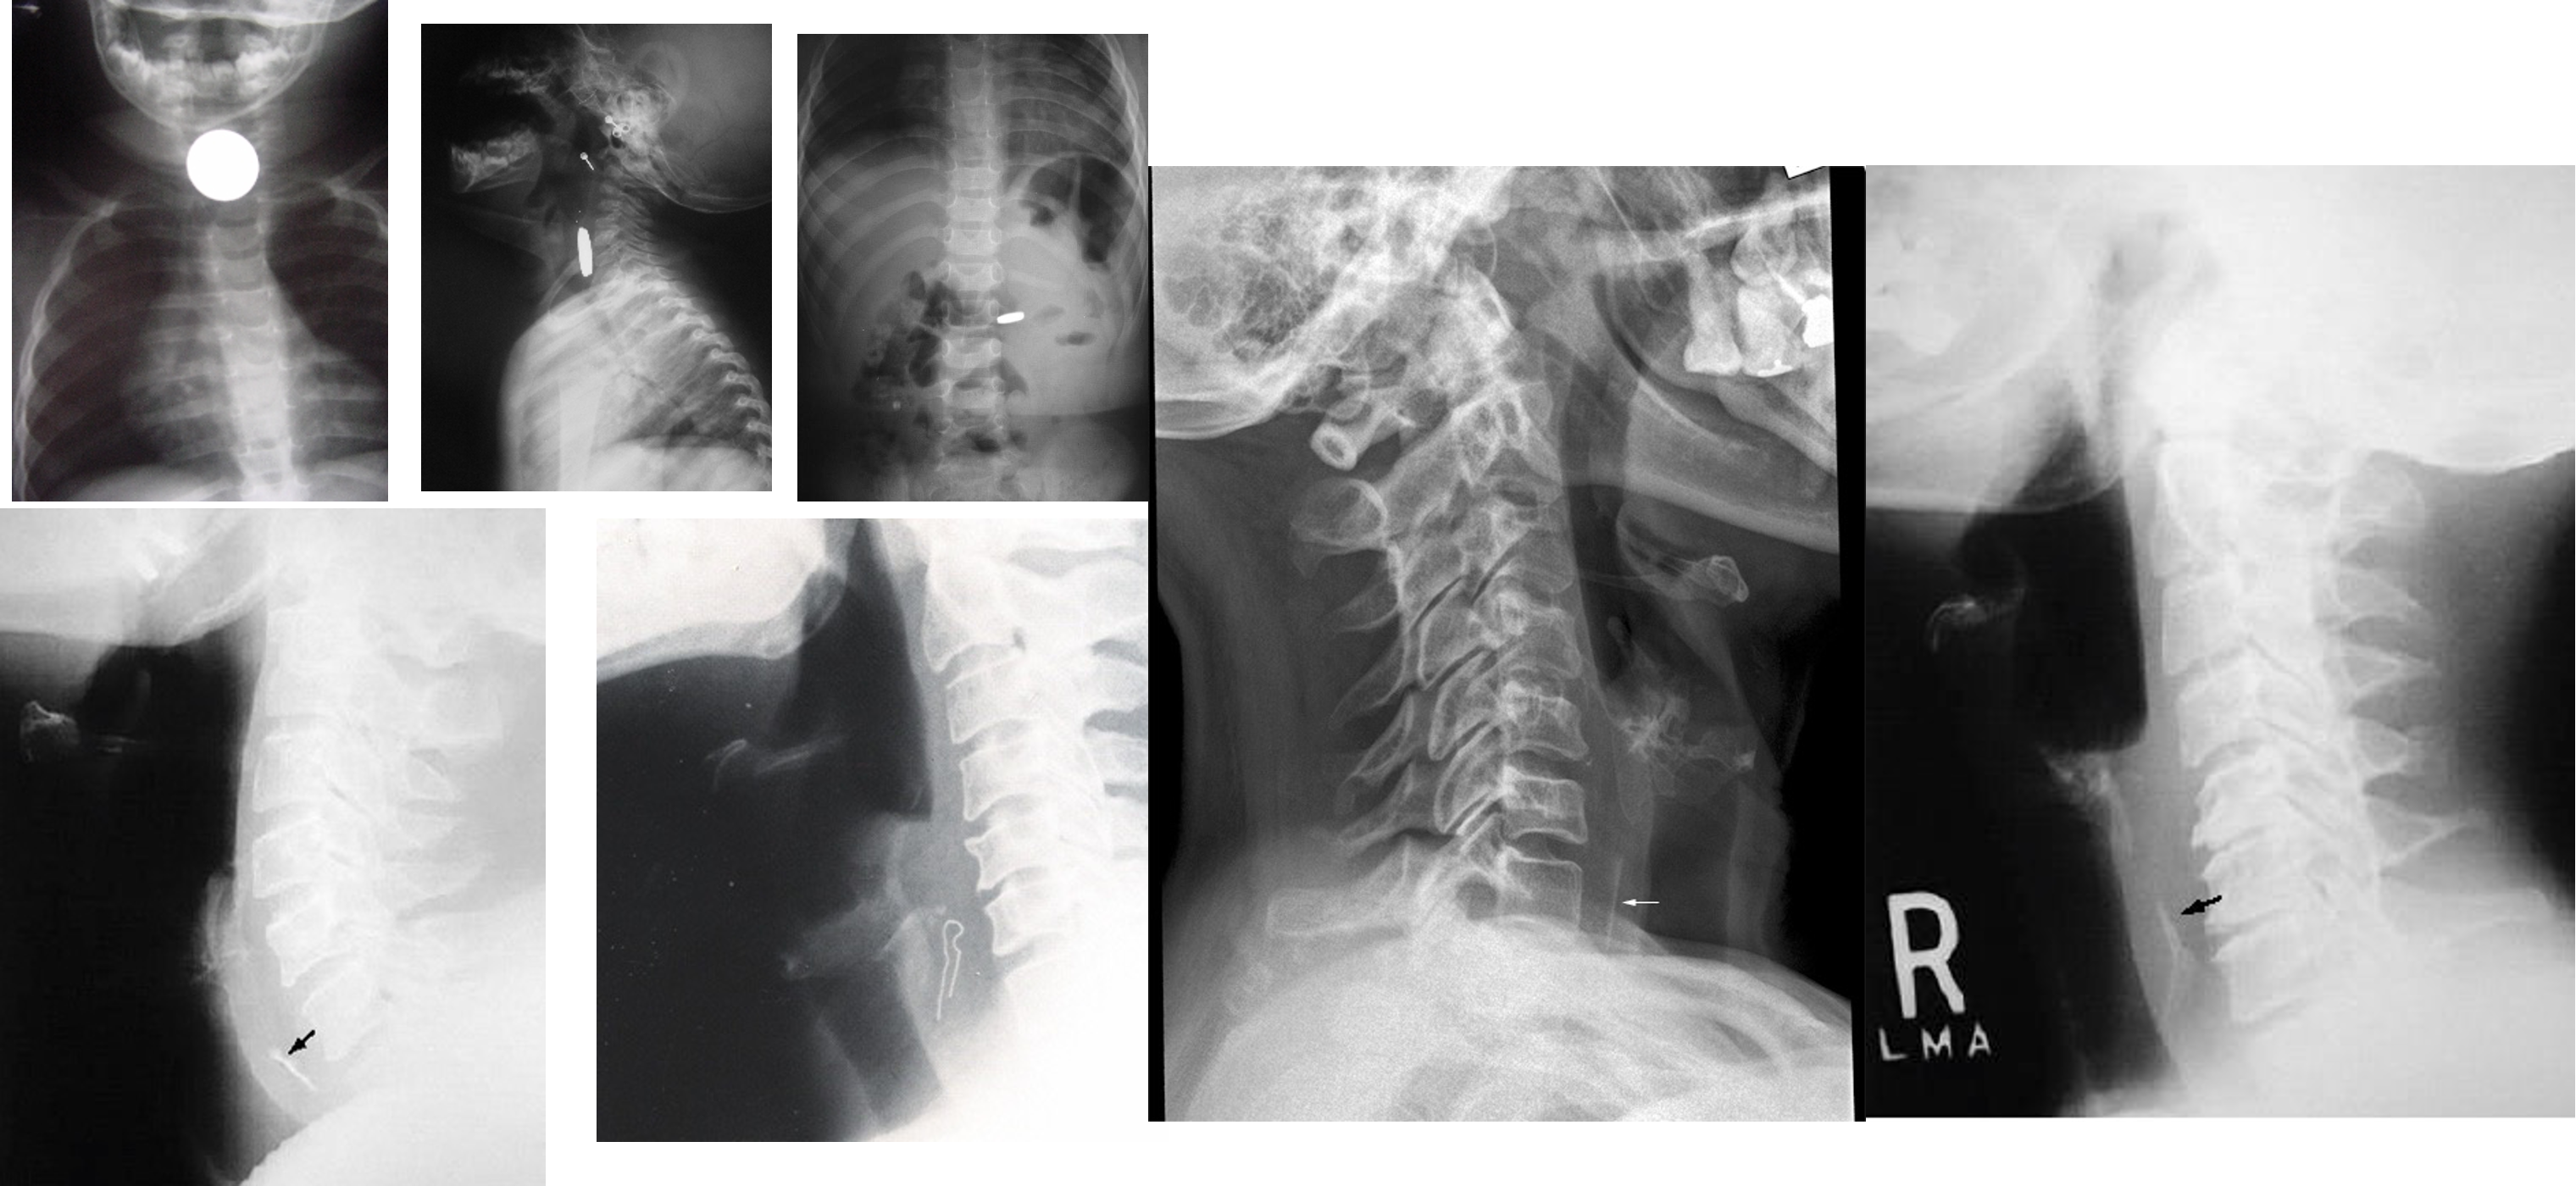

OSPE

Radiology of Tracheobronchial F.Bs

- 2 Radio-opaque FB

4 Collapse

- Bronchopneumonia